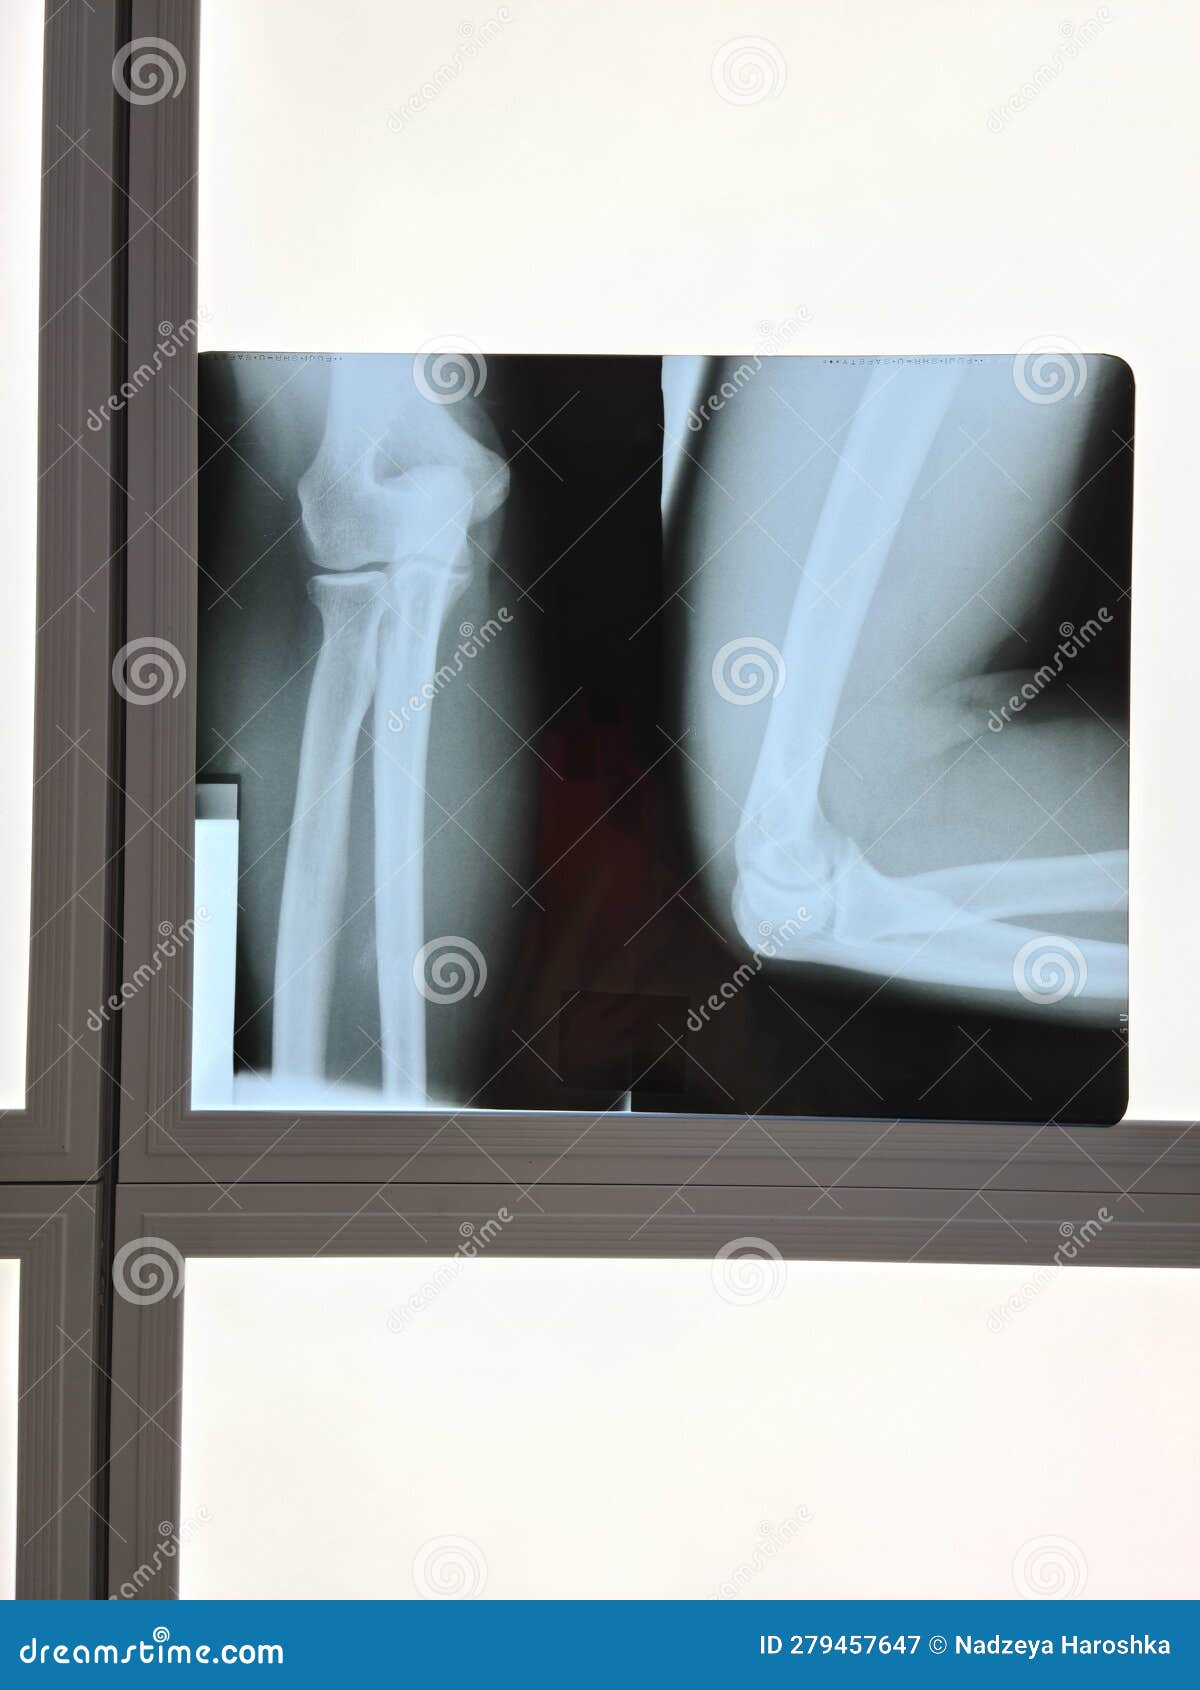

From www.dreamstime.com

Film Xray Elbow and Show the Elbow Stock Image Image of human What Will Elbow X Ray Show Learn how to systematically interpret elbow radiographs using a checklist of soft tissue, cortical, trabecular, alignment, joint and. Learn about the elbow series, a set of radiographs taken to investigate elbow joint pathology, often in the context of trauma. Your elbow bones include the upper bone of your elbow joint (humerus) and the lower bones of your elbow joint (radius. What Will Elbow X Ray Show.